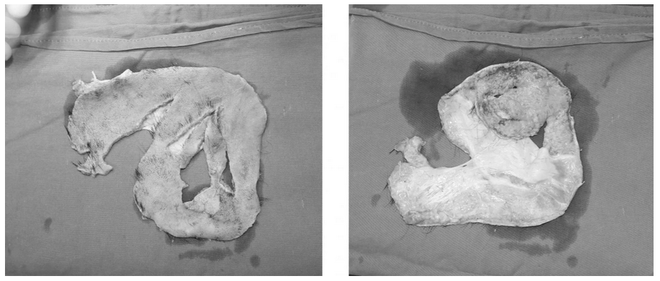

Cứu sống 1 phụ nữ bị lóc toàn bộ da đầu nguy kịch nhất trong y văn ảnh 2Toàn bộ da trán và da đầu của chị B. bị lột đứt phăng rời khỏi hộp sọ, cuốn nghiền nát trong máy khoan. (Ảnh: PV/Vietnam+)

Tại Bệnh viện Bạch Mai, bệnh nhân khẩn trương được làm các xét nghiệm cần thiết cũng như hồi sức để toàn trạng được ổn định. Sau 1 giờ 30 phút, bệnh nhân được đưa vào phòng phẫu thuật. Do tính chất phức tạp của ca phẫu thuật khi mảnh da đầu của bệnh nhân B. bị đứt rời thành 2 mảnh, dập nát, nhiều dị vật, các phẫu thuật viên được chia thành 3 kíp: 2 kíp làm sạch và chuẩn bị mạch tại mảnh da đầu, 1 kíp phẫu thuật tìm và chuẩn bị mạch nhận.

Tiến sỹ Thái Duy Quang - Khoa Phẫu thuật Tạo hình thẩm mỹ nhớ lại: “Khi tiếp nhận bệnh nhân, nhìn đống da đầu bầy nhầy, long tróc, chia hai mảnh nhiều chỗ rách nát, băm vằm ra từng mảnh nhỏ, y bác sỹ đều lo sợ cuộc phẫu thuật gặp nhiều khó khăn. Thêm vào đó việc mảnh ghép đã đứt rời 12 tiếng, quá mất thời gian vàng 6 tiếng sau khi mảnh da đầu bị đứt rời thì cơ hội sống của mảnh ghép hầu như còn rất ít. Khi mở băng, nhìn toàn bộ xương sọ trơ khấc, không được phủ một chút tóc hay màng xương, chúng tôi càng áp lực.”